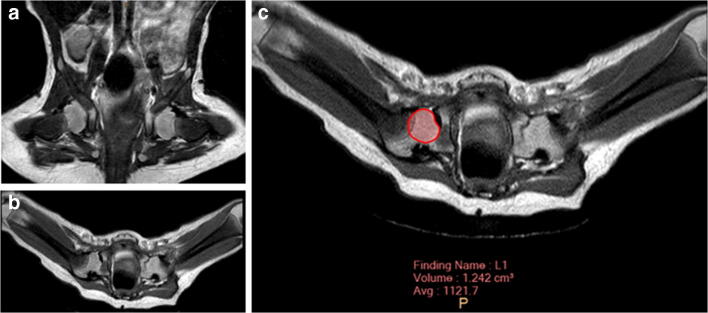

For MRI, patients were placed in supine position with the previously applied pelvic cast. In most cases, images were obtained without additional anaesthesia using a Philips Ingenia System (Philips Healthcare, Best, The Netherlands) at field strengths of either 1.5 Tesla (T) or 3.0 T. T2-weighted turbo spin echo (TSE) sequences in the transverse and coronal plane were used to evaluate the correct reposition of the hip. The slice thickness was set to 2.5 mm. For measuring femoral head volumes (Fig. 1) and acetabular diameters (Fig. 2), IntelliSpace Portal (Version 10.1, Philips Medical Systems, Best, Netherlands) was used. For volumetry, the femoral head was segmented in each axial slice. The largest acetabular diameter was also measured in axial sequences. Acetabular opening area was calculated by Ao = πd2/4. All measurements were performed by three radiologists with routine in MR imaging for both DDH and contralateral, healthy hips. For estimation of intra-observer reliability, measurement was repeated six months after the initial measurement.

Fig. 2.

Acetabular diameter of both sides was measured in the transversal plane of the largest diameter. The hip of the left side was dislocated and CR was successful